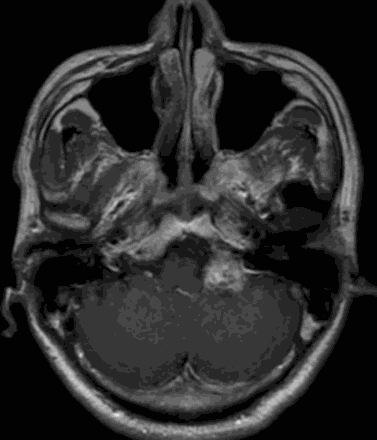

CASE 1 [复发听神经瘤 ]

患者:男, 57y

五年前因听力下降,核磁共振检查发现听神经瘤

最大径约3.0cm,行右侧听神经瘤切除术

现患者出现右边脸部麻木6个月,复查磁共振提示肿瘤复发

最大径约3.9cm

术前影像资料